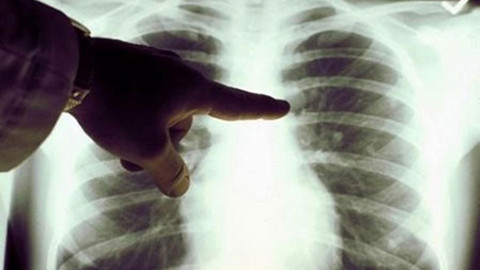

Uzman isim uyardı! Akciğer kanserinde erken tanı hayat kurtarır

ERKEN TANI TEDAVİ BAŞARISINI ARTIRIYOR

Erken evrede teşhis edilen vakalarda tedavi sürecinin çok daha başarılı ilerlediğini kaydeden Ölmez, “Hastalığı başlangıç aşamasında yakaladığımızda cerrahi veya radyocerrahi yöntemleriyle oldukça yüksek oranlarda sağkalım elde edilebiliyor. Tanı ne kadar erken konulursa uygulanan tedaviler o kadar etkili oluyor” diye konuştu.